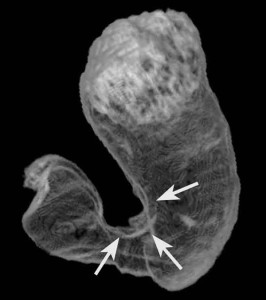

Il tumore gastrico origina nel rivestimento interno dello stomaco, ha uno sviluppo lento, di solito nell’arco di diversi anni, e spesso non viene scoperto subito. ulcere_gastricheDa anni non ci sono significativi progressi delle terapie, ma una nuova speranza viene da un farmaco “affama-tumori” presentato al congresso di oncologia Asco a Chicago. Ramucirumab e’ un anticorpo monoclonale strutturato per inibire in maniera diretta l’angiogenesi, ovvero la formazione di nuovi vasi sanguigni che apportano sangue alle cellule tumorali.